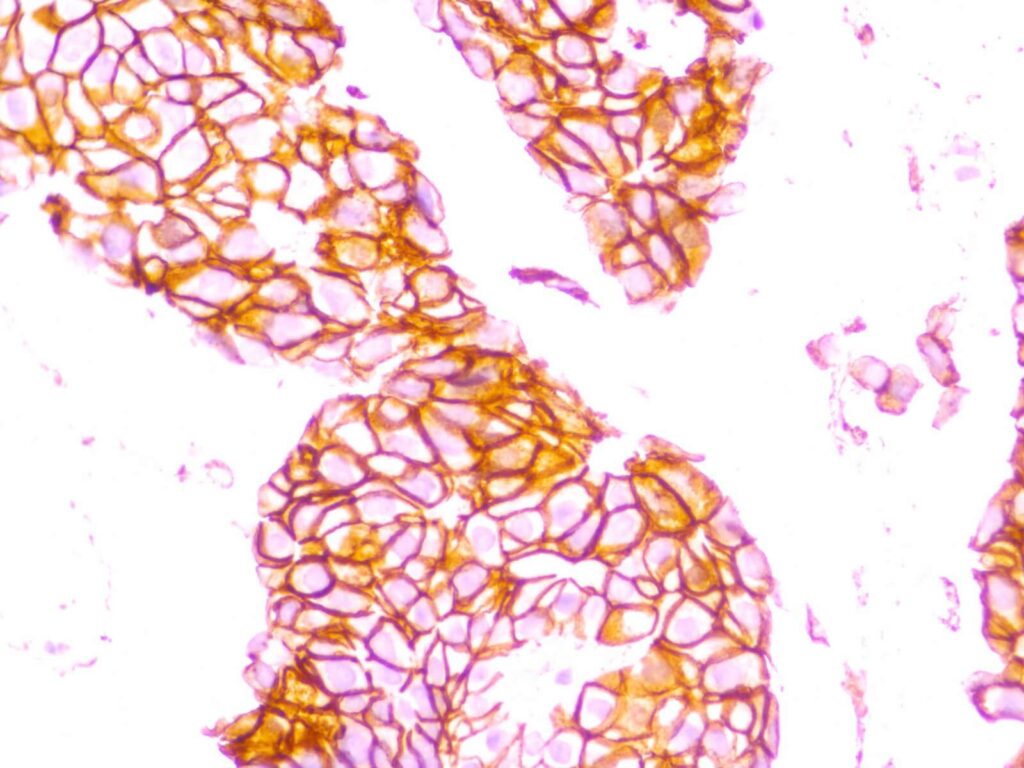

Special histological procedures available include various special stains and immunohistochemistry (IHC) to further aid or refine diagnosis.